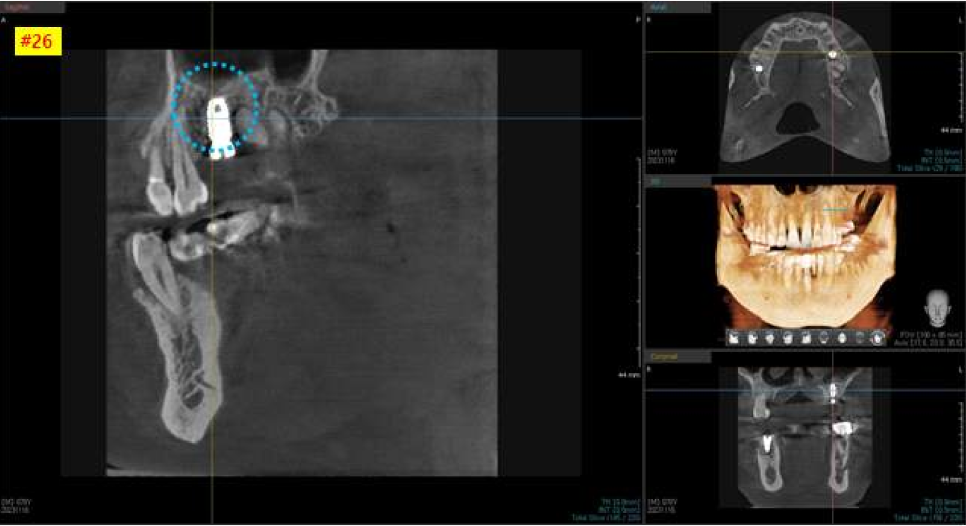

왼쪽 위 큰어금니 CT 사진을 보시면

비교적 뼈가 하얗게 잘 차있는 모습을 볼 수 있습니다.

인접치 관계를 고려해서

가장 이상적이고 안전한 위치를 찾아

적정한 두께와 길이의 임플란트를 선택합니다.

먼저 왼쪽 위 치아 수술을 먼저 진행했는데요,

파노라마 엑스레이랑 3차원 CT 사진을 보시면

아주 잘 심어진 상태를 보실 수 있습니다.

염증이 없는 상태여서, 뼈이식 없이 즉시 임플란트 식립을 진행 하였습니다.

수술 후, 초기고정력도 높게 잘 나왔습니다.